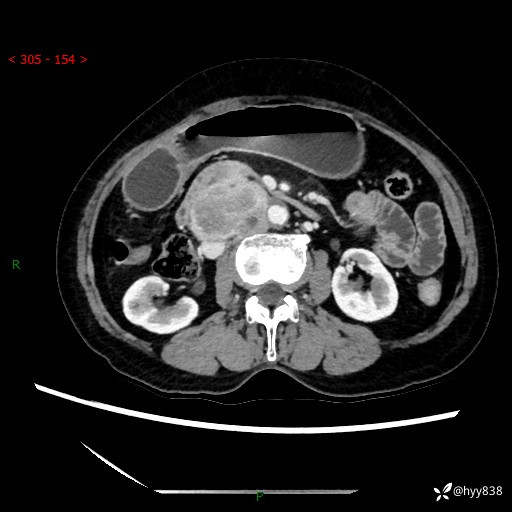

71岁/女,腹痛1月余。腹膜后肿物,间质瘤 VS 副节瘤 VS 平滑肌肉瘤---(有结果)

【患者信息】:71岁/女

【主诉】:腹痛1月余

【现病史及既往史】:患者于1月前无明显诱因出现右下腹部疼痛不适,呈阵发性隐痛,尚可耐受,放射至后背部及腰部疼痛,伴排便困难,不伴其它部位疼痛,无嗳气,无不洁饮食,无黑便,无恶心、呕吐、腹胀腹泻、呕血、发热、寒颤、厌油、黄疸,多次就诊于当地区太湖医院拍片示: 行抗炎等对症支持治疗,效果尚可。现患者上述不适症状明显进一步加重,为求进一步治疗遂来我院门诊就诊,门诊以“十二指肠肿瘤?”收住我科。 起病以来,精神、睡眠可,食欲可,大便异常、小便正常,体力、体重无明显下降。

【检查】:腹部CT增强扫描(外院CT平扫)